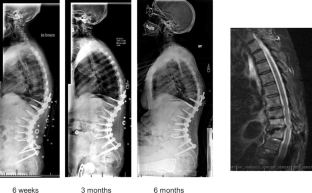

Fig. 3